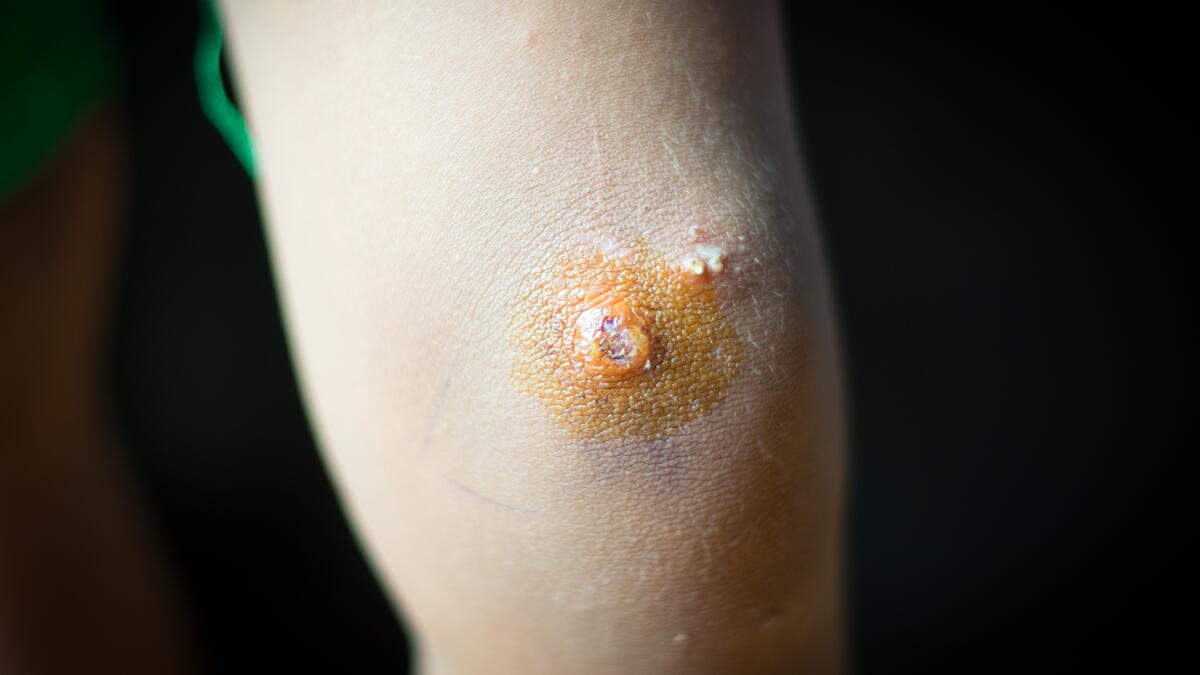

Wells syndrome was described by a British dermatologist from London in 1971, Dr George Crichton Wells -Eosinophilic Cellulitis typically presents with red, swollen, and itchy skin lesions that may resemble cellulitis or

image size: 1145x890